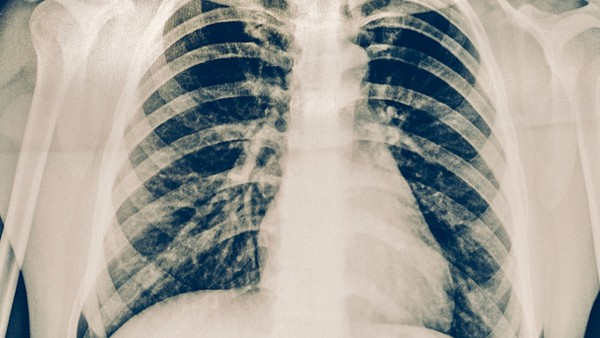

慢性肺炎是一種常見的呼吸道疾病,對老年人的肺健康有害。一旦發(fā)病,就會出現(xiàn)咳嗽、咳痰、呼吸急促等癥狀。隨著病程時間的延長,肺功能也會受到影響。因此,有必要積極開展治療工作,及時治療,以延緩病程時間。治療老年慢性肺炎的措施是什么?